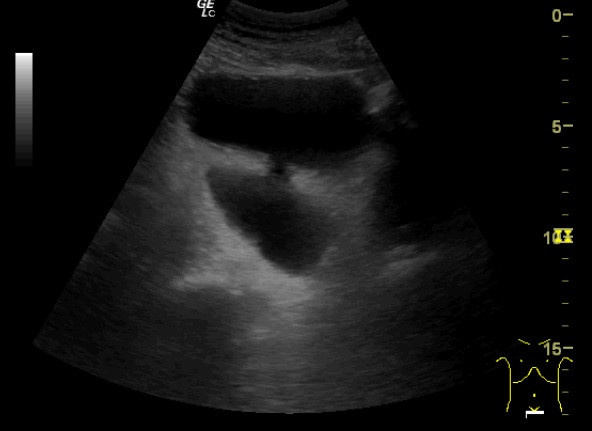

Hallazgos ecográficos

Glándula prostática de 4,28 x 5,81 x 4,57 cm (Figura 1). Volumen prostático: 59,45 ml. Pared de vejiga no engrosada. Se objetiva divertículo vesical (Figura 2) único localizado en pared postero lateral. No se observan lesiones intravesicales ni tampoco en la luz del divertículo (Figura 3). Volumen posmiccional 240 cc.